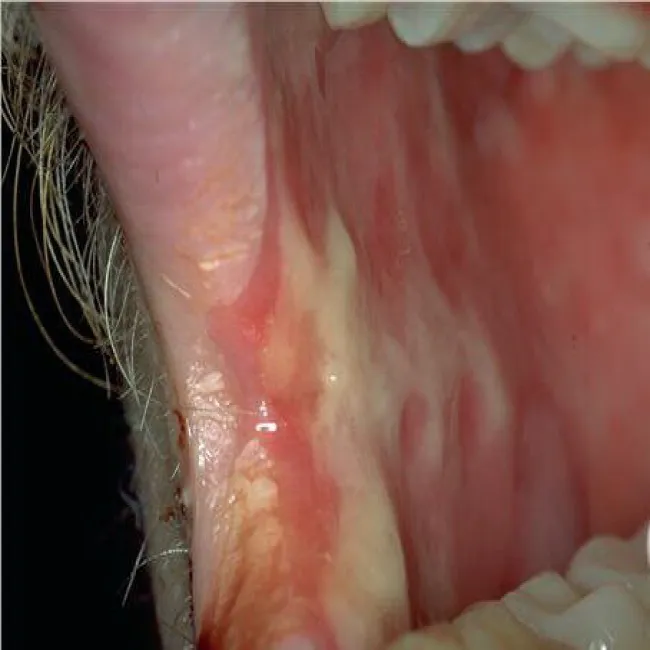

Jama ustna zespół Stevensa- Johnsona

Zespół Stevensa-Johnsona

Jama ustna